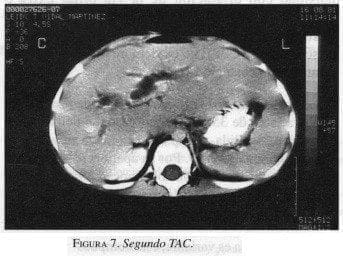

Dos años después la US (figura 6) y TAC (figura 7) de control demostraron regresión completa del tumor, persistiendo la dilatación moderada de la vía biliar; además se presentó salida accidental del tubo sinfín. A la fecha la paciente se encuentra asintomática.